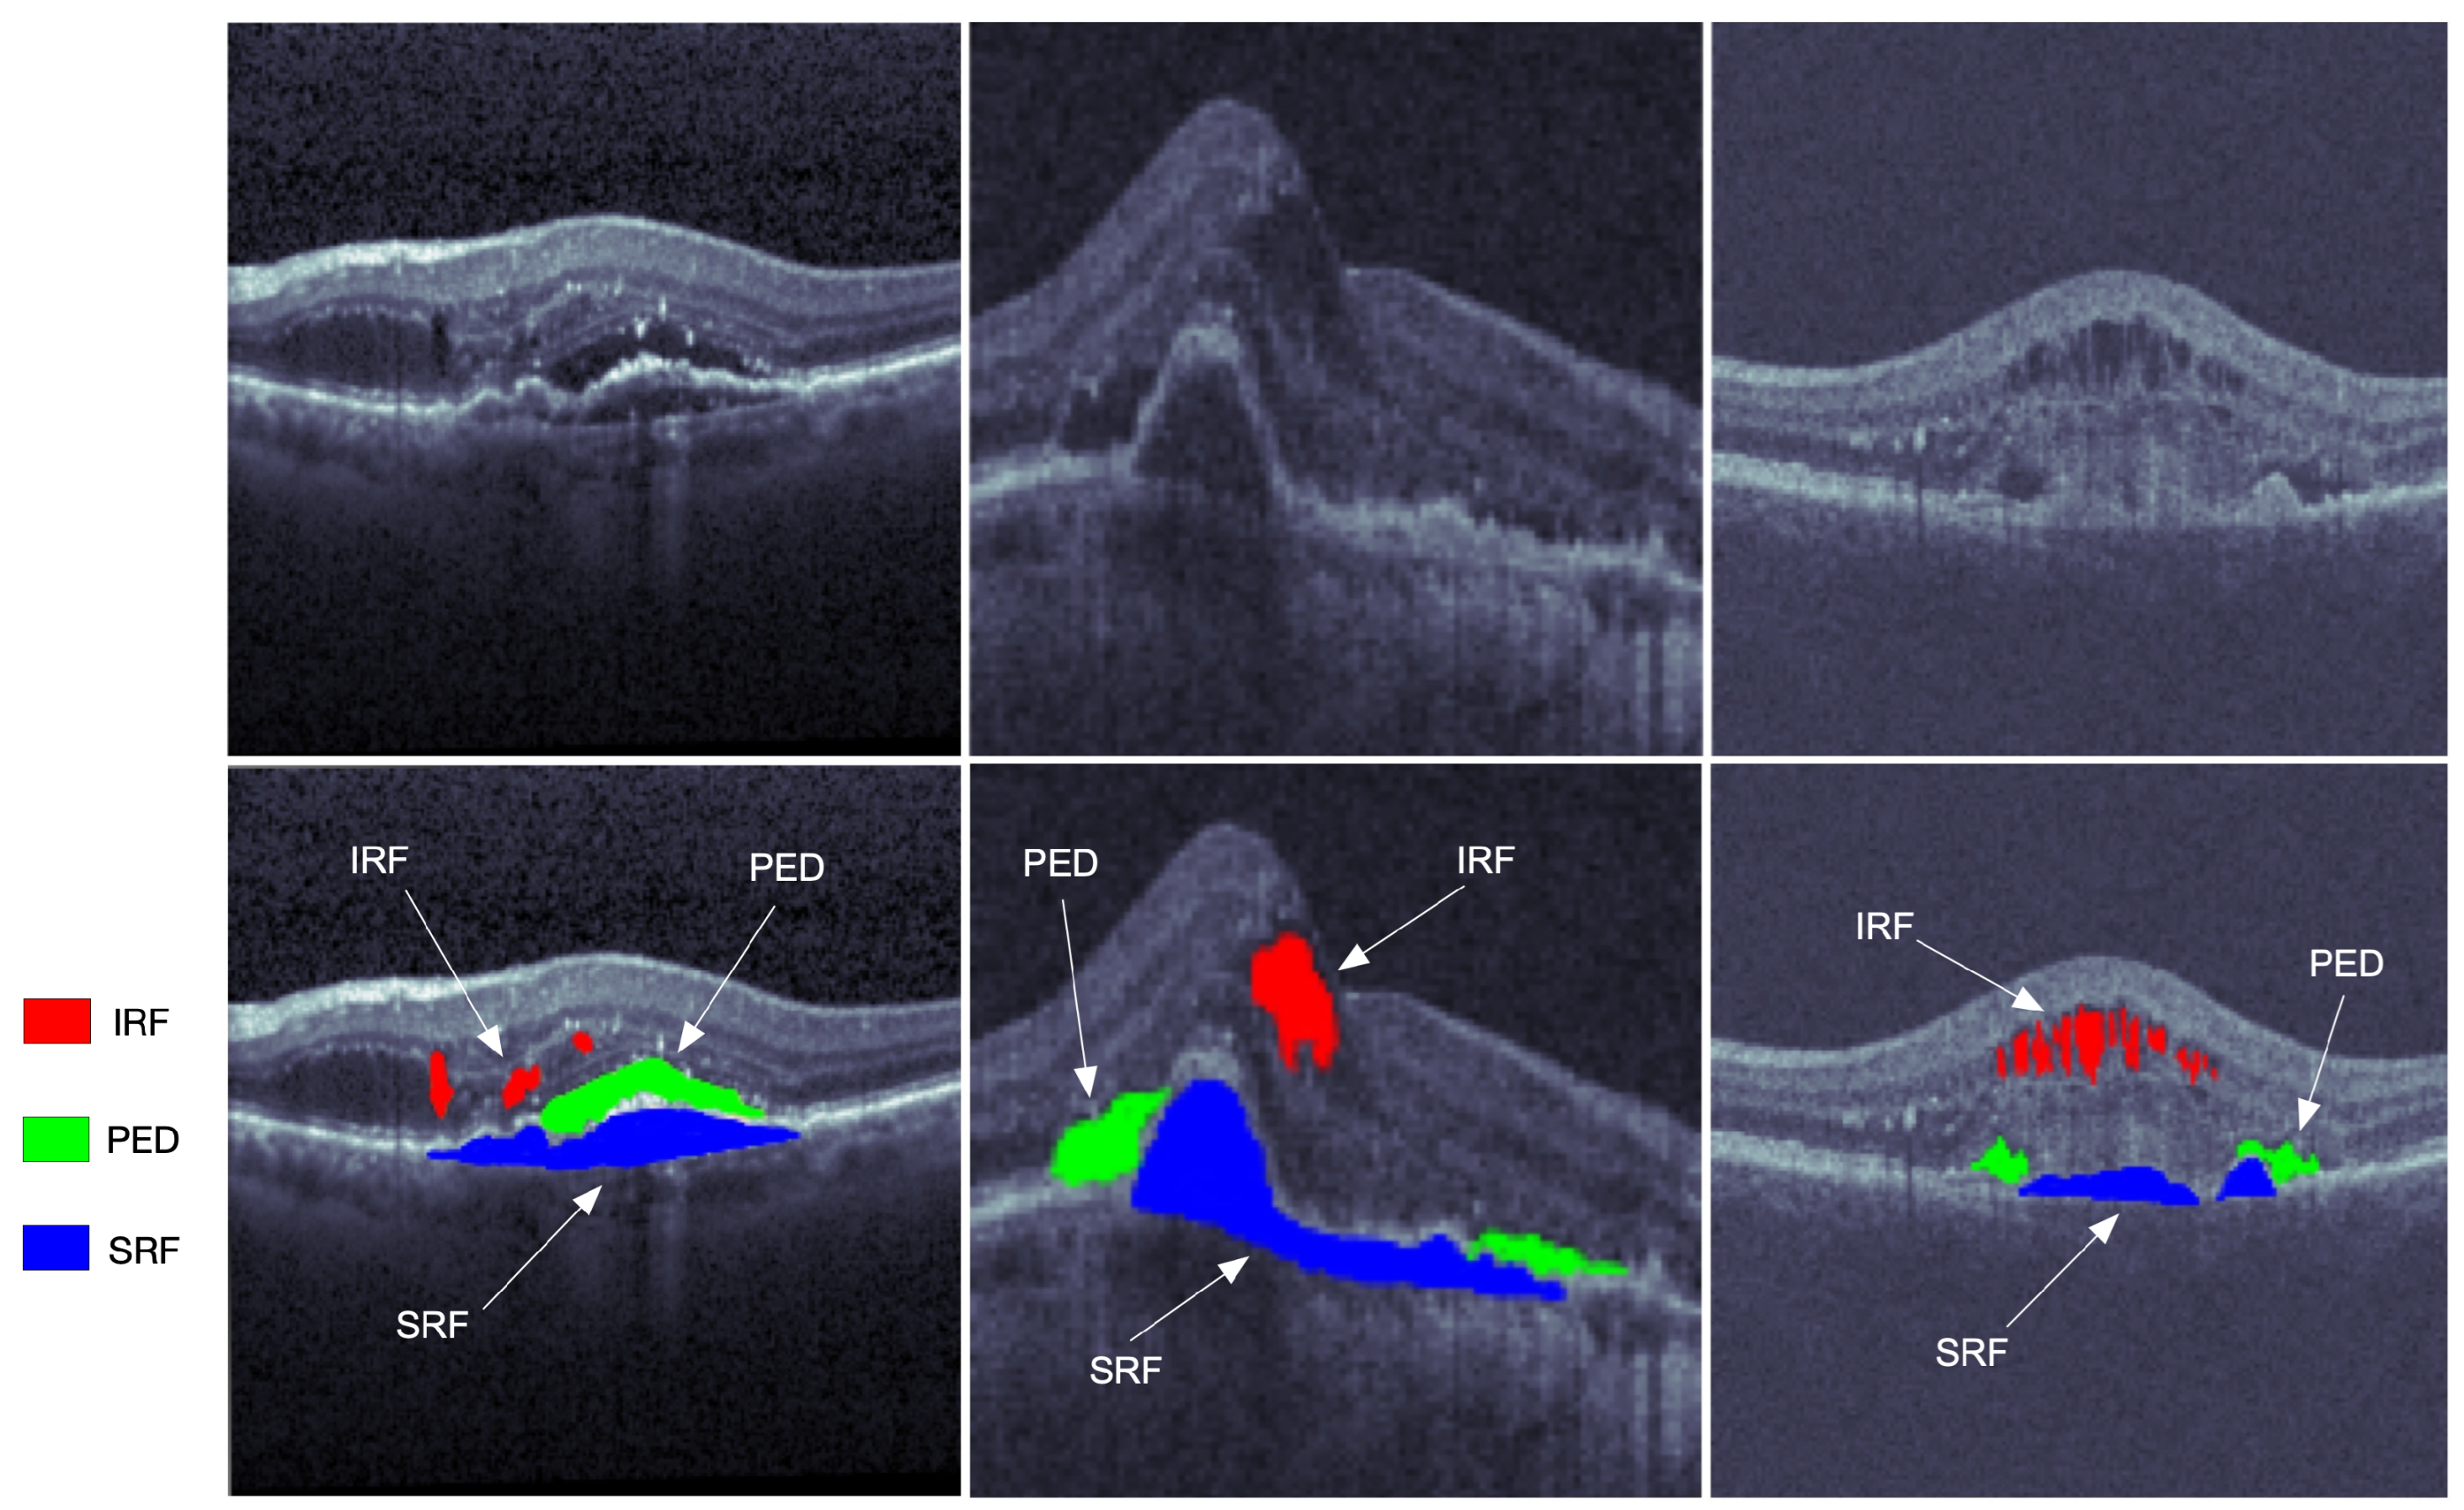

Optical coherence tomography (OCT) is one of the most widely used medical imaging technologies, which has been rapidly developing in the past three decades. Such an imaging technique was first proposed by Huang et al. [1] in 1991. The OCT technique utilizes the basic principle of the low coherent light interferometer to detect the backscattered near-infrared light and reconstruct the depth profile of the biological tissue sample. Its penetration depth is hardly limited by the transparent refractive medium of the eye. Furthermore, the OCT technique can identify the anterior segment and display the morphological structure of the posterior segment. The OCT modality is a good choice for cross-sectional imaging of the retina because its high resolution facilitates a clear visualization of retinal structures. From the images of the retinal structure obtained by the OCT modality, the fluid area can be visualized with different reflectivity measures from the surrounding tissues. The OCT image processing and analysis may help distinguish various conditions of retinal fluids and evaluate the progression of retina pathology. It has a brilliant prospect in the applications of retinal pathology diagnosis, follow-up observation, and treatment effect evaluation of intraocular diseases. Some typical segmentations of OCT images are shown in Figure 1.

Figure 1.

The OCT retinal images from left to right are from the three vendors of Cirrus, Spectralis, and Topcon in the RETOUCH dataset [2]. The images in the first row are not manually labeled, while the red, blue, and green segmentations on the second row represent the intraretinal fluid (IRF), subretinal fluid (SRF), and epithelial detachment (PED), respectively.